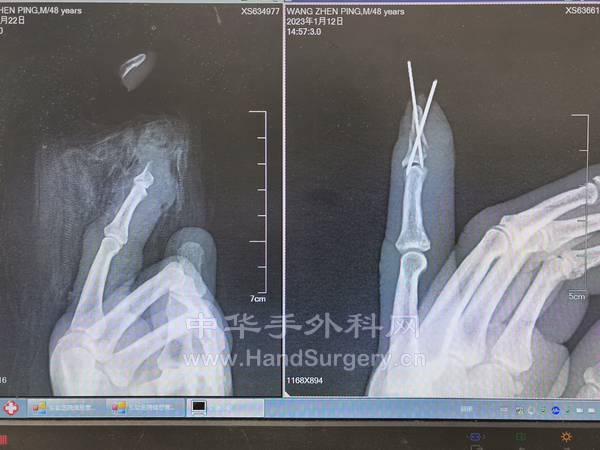

本帖最后由 zhangwenlong 于 2023-1-16 19:55 编辑

两个阳性大夫,两个阳性护士,一个阳性麻醉师,给一个阳性病人做手术。手术室里除了监护仪的心跳声,就是此起彼伏的咳嗦声……

IMG_20230112_154436.jpg